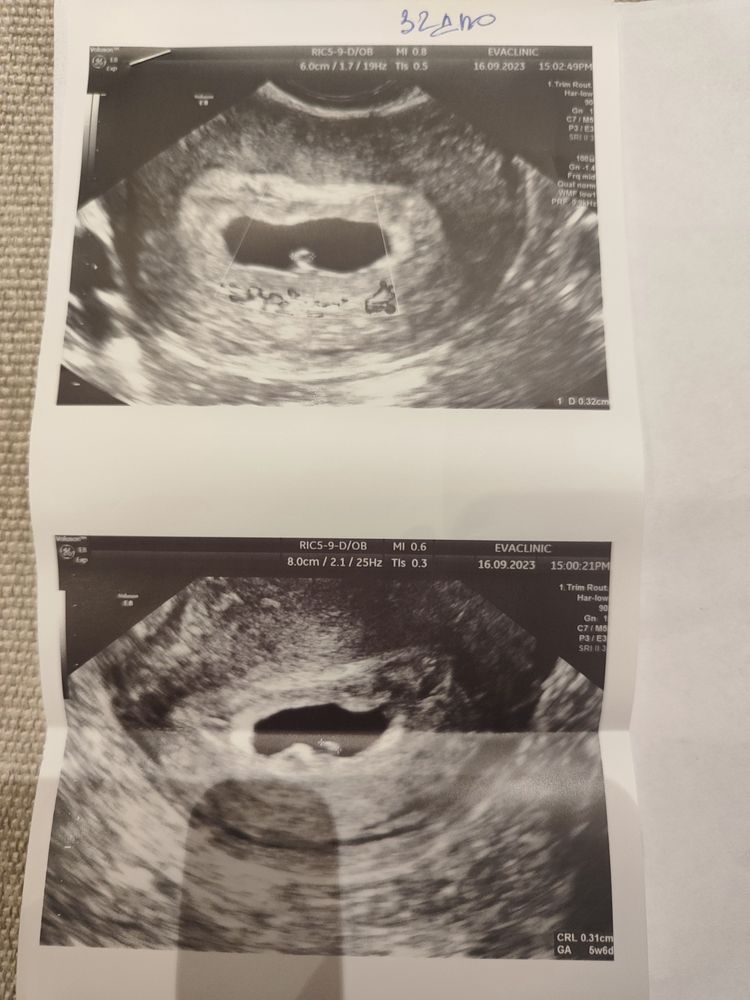

Была на УЗИ:

22.дпо -(4.2. ак.нед)- эмбриона нет, жм 3.2. ПЯ- 6.7

32 дпо( 6.2 нед) эмбриона нет, жм 3.2. (но врач сомневалась) ПЯ 20.0 неправольной формы (ХГЧ за день до 24тыс.) - ставит замершую, отправляет на чистку

Прикрепляю УЗИ 32 дпо и 34 дпо-... Может кто-то что-то поймет.